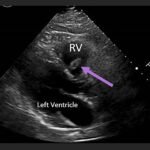

Endovascular coil embolization continues to become a more frequent modality of addressing hemorrhage and bleeding in patients. Migration refers to the coil unraveling or moving from the original embolization site. Migration of a coil is a known complication which can lead to serious consequences based on where the coil migrates. Despite increasing efforts to improve safety and technique, the risk of migration remains. We present a case of an embolization coil that migrated to the right ventricle, which was incidentally found roughly 2 months after undergoing an interventional radiology procedure for gastric variceal bleeding. The patient presented to the emergency department with dyspnea and abdominal pain. Unique images were obtained during his visit and in subsequent follow-up. As use of vascular embolization coils continues to become more commonplace, understanding the risks and complications of these procedures remains an important aspect of providing care for patients once they have left the interventional radiology suite. Coil migration should be a differential to consider in patients who present to the emergency department with signs or symptoms of arrhythmia or pulmonary embolism who have undergone a coil embolization procedure.